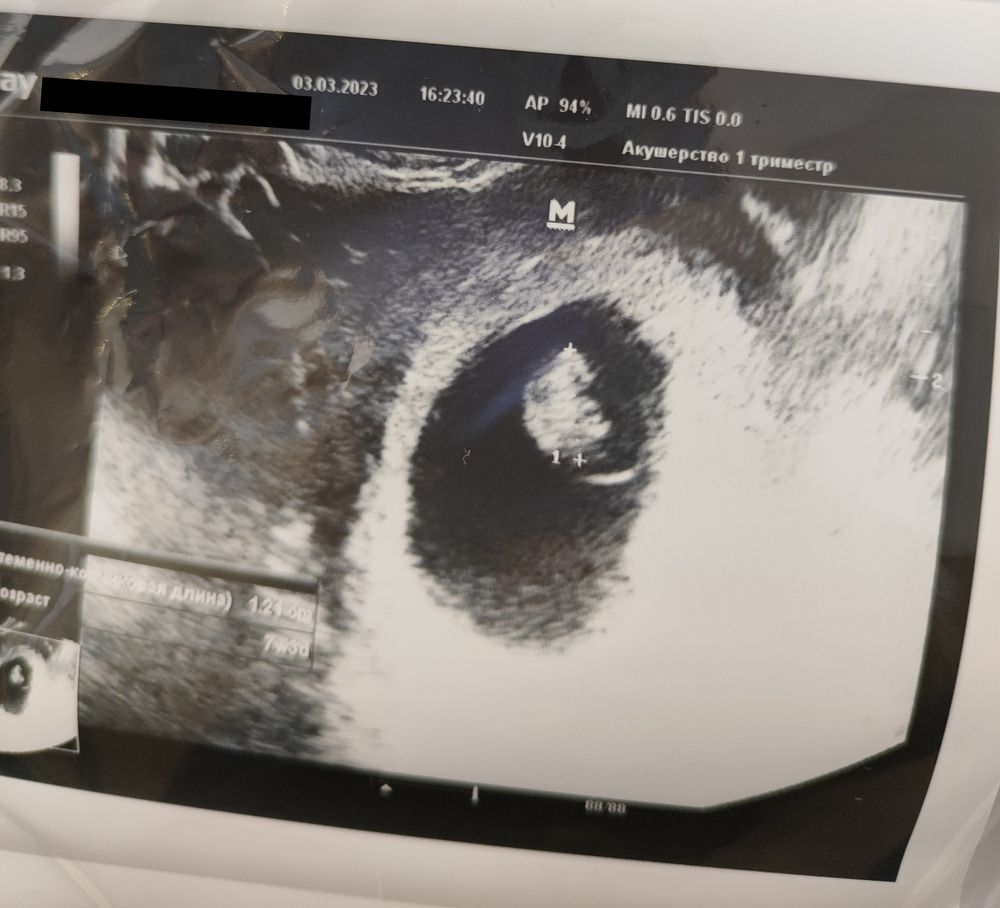

УЗИ💙7 недель и 3 дня моей крошке🌍

И день рождения у меня🎉 и на УЗИ сходила, проведала крошку, включили сердечко (168 ударов в минуту💙).

🌿СВД 37.3 мм

🌿КТР 12,1 мм

🌿ЧСС 168 уд/мин

Ни отслоек, ни гематом тьфу-тьфу, только тонус по задней стенке. А так мы с мужем счастливы как никогда 🥰🥰🥰